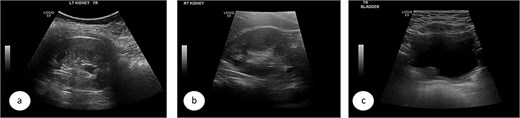

A 7-year-old child was referred to the pediatric urology clinic due to a history of recurrent febrile urinary tract infections and urge incontinence, accompanied by constipation (Bristol 2). These symptoms persisted despite meticulous conservative management, including urotherapy. Ultrasound (US) revealed bilateral pelviectasis and voiding cystourethrogram (VCUG) revealed bilateral Grade 3 VUR and a mildly trabeculated bladder wall, whereas the urethra appeared normal (Fig. 1a–d). A DMSA renal scan verified bilateral renal scarring, revealing differential renal function of 40% in the right kidney and 60% in the left kidney (Fig. 1e). Endoscopic intervention was warranted, and 1 ml of Deflux was injected on the left side and 0.6 ml on the right side, successfully creating an adequate mound. The patient was discharged in stable condition for several hours following surgery, despite being anuric. Subsequently, the patient experienced intense abdominal pain and was admitted to the emergency department. The physical examination was uneventful, except for moderate hypertension. The urinalysis revealed microscopic hematuria. His urea level was 16 mmol/L, and creatinine rose to 126 umol/L from a baseline of 40 umol/L. Post operative US at emergency room demonstrated increased bilateral hydronephrosis (Fig. 2).

Ultrasound images showing the left (a), and right (b) kidneys and the urinary bladder (c). VCUG is showed bilateral grade 3 VUR (d). DMSA images are shown in (e).